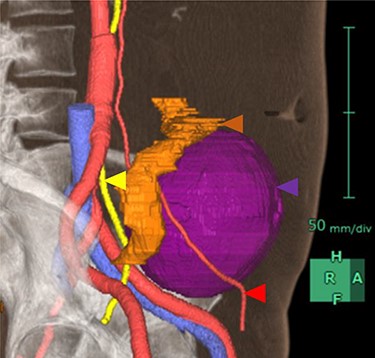

As the tumor was close to the left ureter and testicular arteries and veins, there was concern about their injury. Hence, we constructed a 3D CT image preoperatively to understand its anatomical positioning and surroundings (Fig. 2). In addition, to avoid left ureter injury, we placed a fluorescent stent in the left ureter preoperatively.

3D image constructed based on CT scans. Purple area is the tumor, yellow area is the left ureter, red areas are the left testicular arteries and orange area is the sigmoid colon.